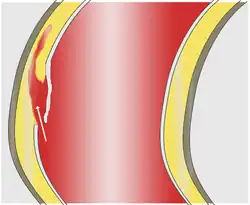

In an aortic dissection, blood penetrates the intima and enters the media layer. The high pressure rips the tissue of the media apart along the laminated plane splitting the inner two-thirds and the outer one-third of the media apart.[27] This can propagate along the length of the aorta for a variable distance forward or backward. Dissections that propagate towards the iliac bifurcation (with the flow of blood) are called anterograde dissections and those that propagate towards the aortic root (opposite of the flow of blood) are called retrograde dissections. The initial tear is usually within 100 mm of the aortic valve, so a retrograde dissection can easily compromise the pericardium leading to a hemopericardium. Anterograde dissections may propagate all the way to the iliac bifurcation of the aorta, rupture the aortic wall, or recanalize into the intravascular lumen leading to a double-barrel aorta. The double-barrel aorta relieves the pressure of blood flow and reduces the risk of rupture. Rupture leads to hemorrhaging into a body cavity, and prognosis depends on the area of rupture. Retroperitoneal and pericardial ruptures are both possible.[28]

The initiating event in aortic dissection is a tear in the intimal lining of the aorta. Due to the high pressures in the aorta, blood enters the media at the point of the tear. The force of the blood entering the media causes the tear to extend. It may extend proximally (closer to the heart) or distally (away from the heart) or both. The blood travels through the media, creating a false lumen (the true lumen is the normal conduit of blood in the aorta). Separating the false lumen from the true lumen is a layer of intimal tissue known as the intimal flap.

The vast majority of aortic dissections originate with an intimal tear in either the ascending aorta (65%), the aortic arch (10%), or just distal to the ligamentum arteriosum in the descending thoracic aorta (20%).

As blood flows down the false lumen, it may cause secondary tears in the intima. Through these secondary tears, the blood can re-enter the true lumen.